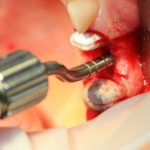

Для получения костного блока мы использовали ультразвуковую пьезохирургическую систему. Это самый удобный и безопасный инструмент для проведения подобных манипуляций. С помощью него мы сформировали и выделили костный блок. Он должен отделяться легким движением остеотома или элеватора. Как это сделать правильно — читай здесь>>

Кстати, если костный блок не отделяется от костного ложа легким движением элеватора, значит он неправильно сформирован или не до конца выделен. Вообще, любое чрезмерное усилие в хирургии — это всегда следствие рукожопия. Если тебе что-то приходится делать с усилием (установка имплантата, удаление зуба и т. д.) — значит ты делаешь это неправильно. Остановись и подумай, что именно.